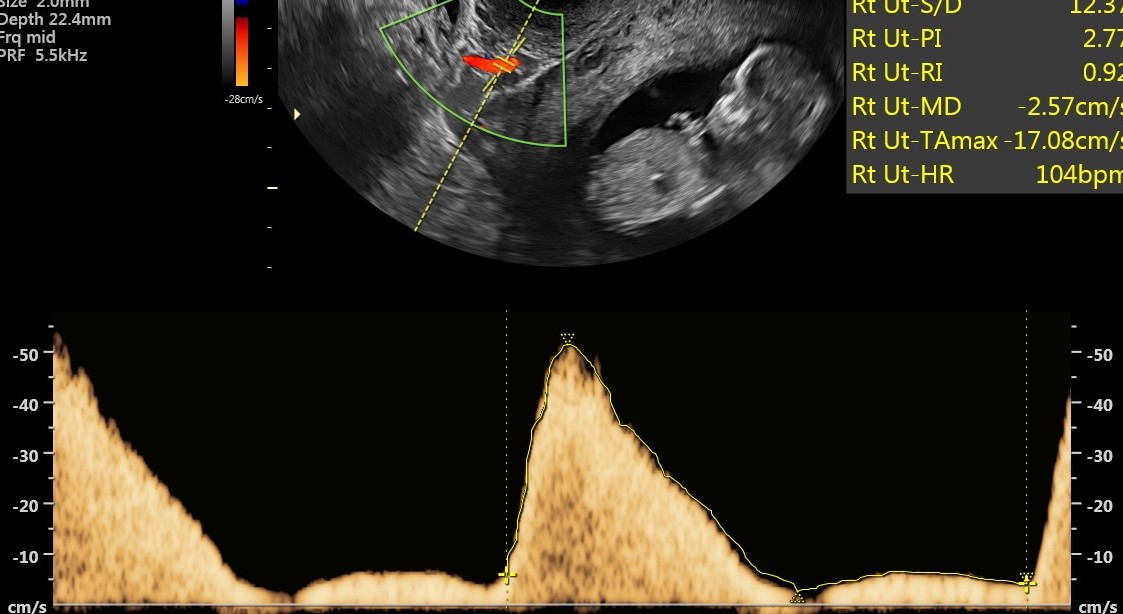

Dzień Zdrowia Aorty - przebadano ponad 40 osób

2022-12-20

Badania przesiewowe aorty organizowane w ramach Dnia Zdrowia Aorty cieszyły się ogromnym zainteresowaniem. Pierwsi chętni do badań ustawili się w kolejce do zapisów już po godz. 8. U żadnej z osób nie wykryto tętniaka. Ta grupa pacjentów może spać spokojnie.

USG Dopplera aorty przeprowadzali dr n. med. Miłosz Kawa i dr n. med. Maciej Wojtuń. Grupą docelową, do której skierowane były badania były osoby po 65. roku życia, u których stwierdzono jednocześnie trzy spośród następujących czynników ryzyka sercowo-naczyniowego: choroba wieńcowa, palenie tytoniu, nadciśnienie tętnicze, hiperlipidemia, płeć męska, występowanie tętniaka aorty brzusznej u rodziców lub rodzeństwa czy przewlekła obturacyjna choroba płuc.